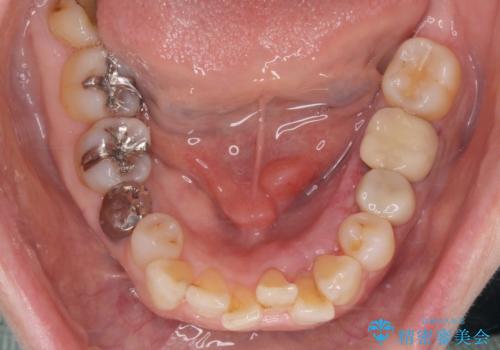

骨隆起除去

- 骨隆起が舌にあたり不快感があるので骨隆起をとりたくて来院。

静脈内鎮静麻酔下で骨隆起を除去を行いました。

骨隆起がなくなり不快感がなくなり大変満足して頂けました。